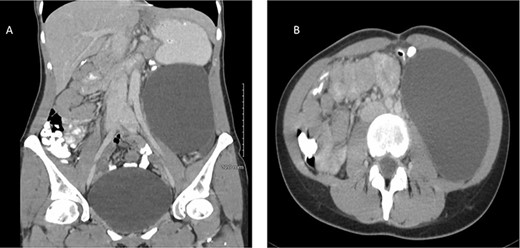

In order to characterize the lesion further, magnetic resonance scan was organized. This demonstrated a 10 × 7 × 15 cm cystic lesion in the left flank between Gerota’s fascia and the descending colon, confirming its retroperitoneal location. The fluid within the lesion was described as simple, with homogenously high T2 and low T1 signals. A possible thin septation was seen within the superior aspect of the cyst, but there was no evidence of any soft tissue component. There was no enhancement within the cyst or its wall (Fig. 2). The most likely differentials at this stage included a lymphangioma or mucinous cystadenoma.

MRI of a 32-year-old woman presenting with chronic abdominal pain and a mass in left iliac fossa. (A) Axial T2-weighted fat-saturated images demonstrate a 10 × 7 × 15 cm cystic lesion in the left flank between Gerota’s fascia and the descending colon. (B) Coronal T2-weighted images confirm the absence of internal nodularity or invasive features.